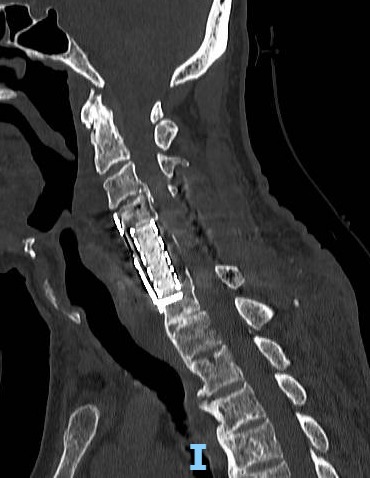

Neurocirurgia Coluna

Intervenções seguras para problemas na coluna vertebral.